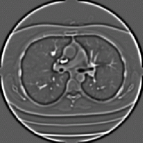

Typical pulmonary nodules of both types are shown in Figure 1. Nodules may have variation in size, shape, intensity profile and attachment morphology.

Refer to caption

Figure 1: Appearance of a solid (a) and nonsolid (b) pulmonary nodule.